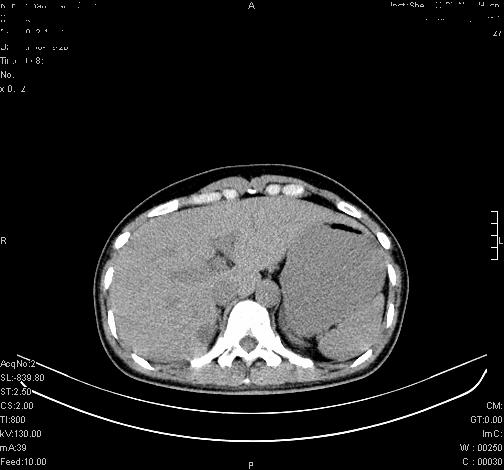

标题: CL0340:【】肾上腺囊肿,比较典型。

患者为年轻女性,查体发现右侧肾上腺囊性占位。无临床体征。

这么漂亮的图像,一看一目了然。典型的右侧肾上腺囊肿,周围有钙化。感谢搂主!

“肾上腺囊肿组织学分为4类:1)内皮细胞性,2)假性囊肿,3)寄生虫性,4)上皮细胞性。其中内皮细胞性最为常见。假性囊肿多为肾上腺内出血后遗留囊腔,囊壁无上皮细胞。寄生虫性多为包虫病引起。上皮性则很少见。”

这么明显的弧形钙化,多考虑包虫病所致的寄生虫性囊肿。

右侧肾上腺囊性密度灶囊壁有钙化。考虑肾上腺囊肿,结核?

右侧肾上腺囊肿,周围有钙化。